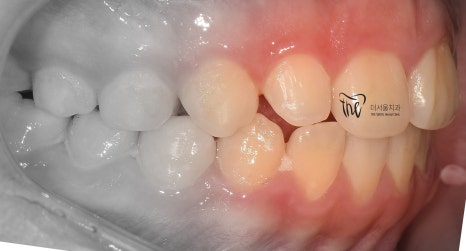

그리고, 정면 및 측면에서 본 모습으로는

살짝 개방교합(Open bite)의 형태를 보여줍니다.

앞니들의 뻐드러짐이 많이 개선이 됨에 따라서,

이제 조금은 가지런한 치열이 만들어지는 것을

보고 계십니다.

다만, 어금니의 위치 이동이 아직 다 되지

않았기 때문에 측면에서 확인했을 때는

치아들 사이에서의 공간이 떠 있으면서,

약간은 1치대 1치 교합 관계가 만들어져

있는 것을 볼 수 있습니다.